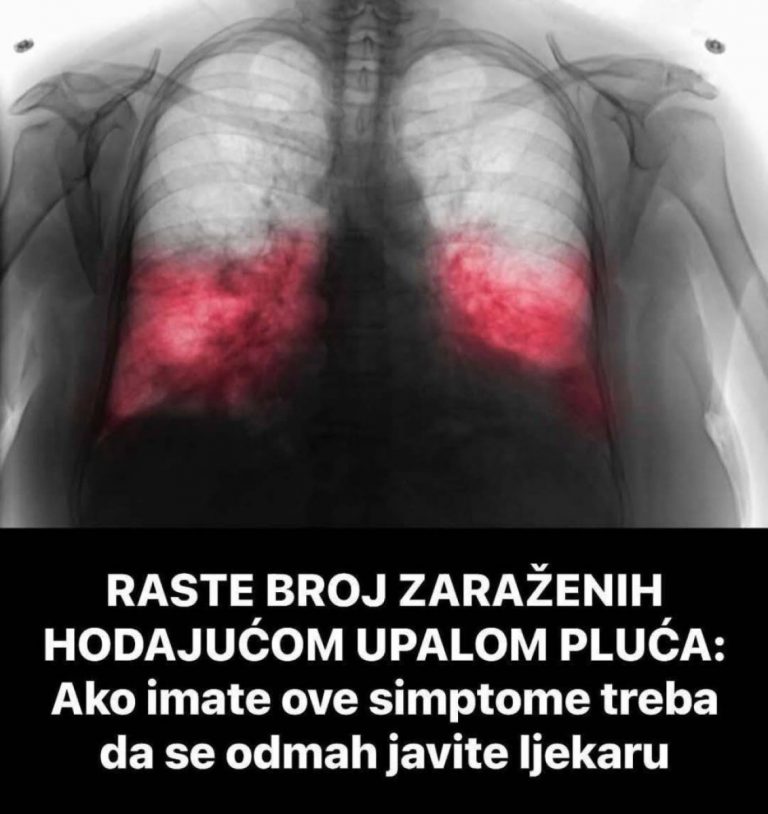

Ako postoji sumnja na hodajuću upalu pluća, doktor će obaviti detaljan pregled, uključujući laboratorijske testove i, ako je potrebno, rendgenski snimak pluća. U nekim slučajevima, doktor može uzeti briseve iz dišnih puteva kako bi se precizno odredio uzročnik. Hodajuća upala pluća obično zahtijeva specifične antibiotike koji ciljaju određene bakterije, jer obični antibiotici često nisu dovoljno učinkoviti.

Neliječena hodajuća upala pluća može dovesti do ozbiljnih problema poput bronhitisa, iscrpljenosti organizma, dugotrajnog kašlja, pa čak i komplikacija kod osoba s hroničnim bolestima. Ako kašalj traje duže od tjedan dana, pogoršava se ili se pojavljuju simptomi poput temperature, bolova u grudima ili otežanog disanja, odmah se treba obratiti doktoru.

Iako se ova bolest često zanemaruje zbog svojih blagih simptoma, vrlo je važno reagirati na vrijeme. Ako se ne liječi, hodajuća upala pluća može izazvati dugotrajne posljedice koje će dugoročno utjecati na pluća i opće zdravlje. Pravovremena dijagnoza i liječenje mogu spriječiti teže komplikacije i pomoći bržem oporavku.